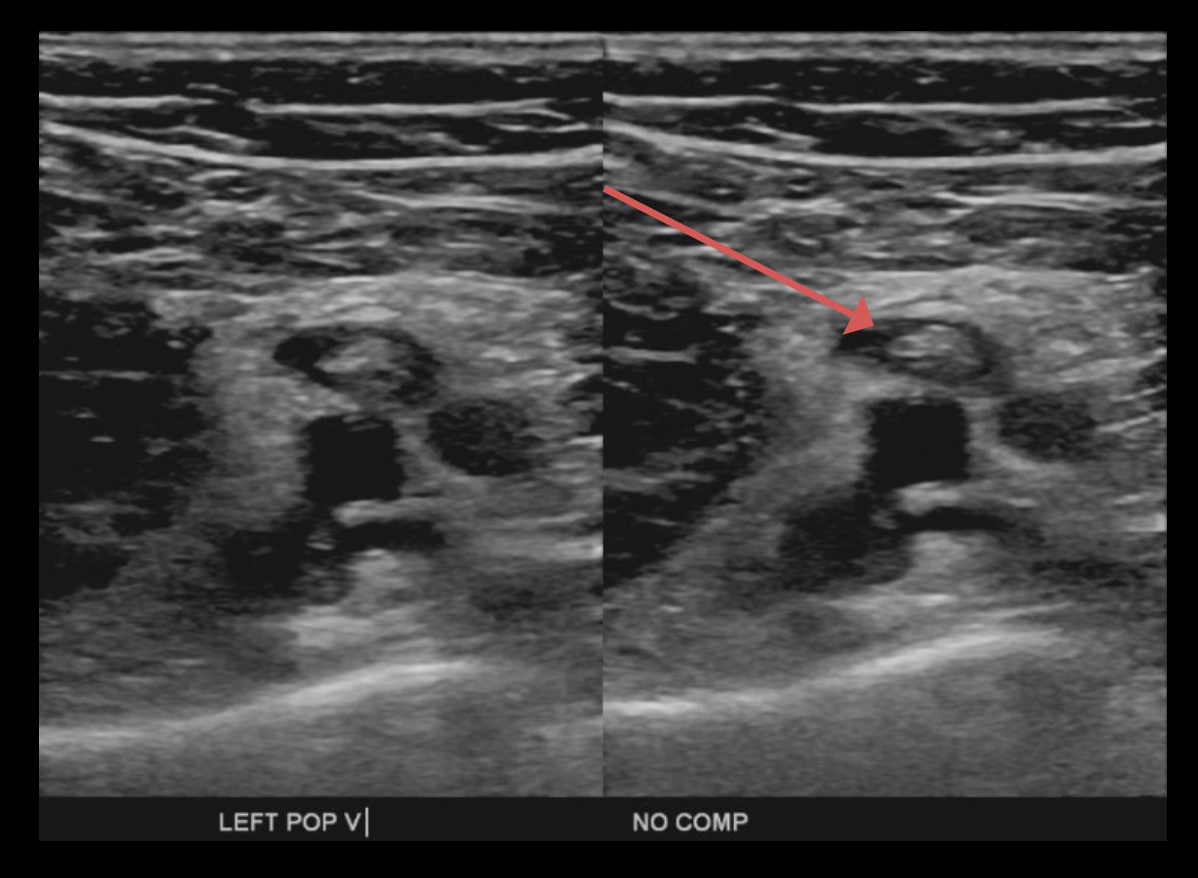

Doppler ultrasonography of the bilateral lower extremities showed an occlusive thrombus in the left distal femoral vein, extending into the popliteal, peroneal, and posterior tibial veins (Figure 2). He also had a mildly elevated troponin level of 0.9 ng/mL, likely from acute cor pulmonale, and his D-dimer level was elevated at 15.98 µg/mL.

Figure 2. Ultrasonography of the left lower extremity showed noncompression of the left popliteal vein.